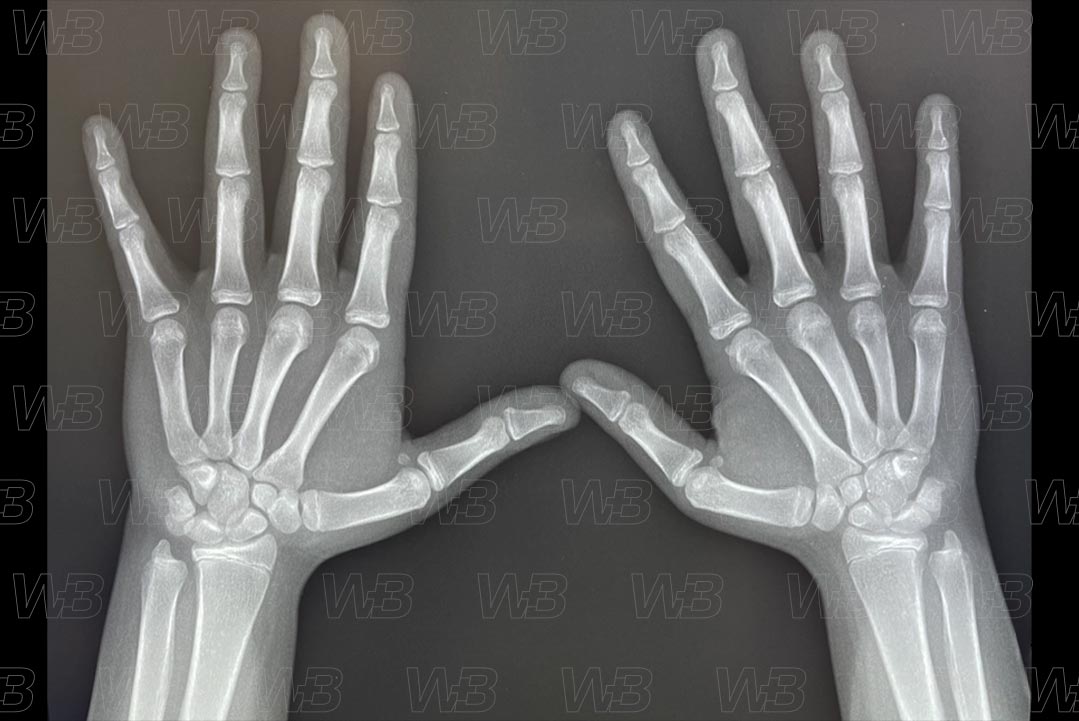

RADIOGRAFIA MÃOS E PUNHOS [cms-watermark]

Feminino

13 anos e 6 meses:

• Fusão das epífises das falanges distais.